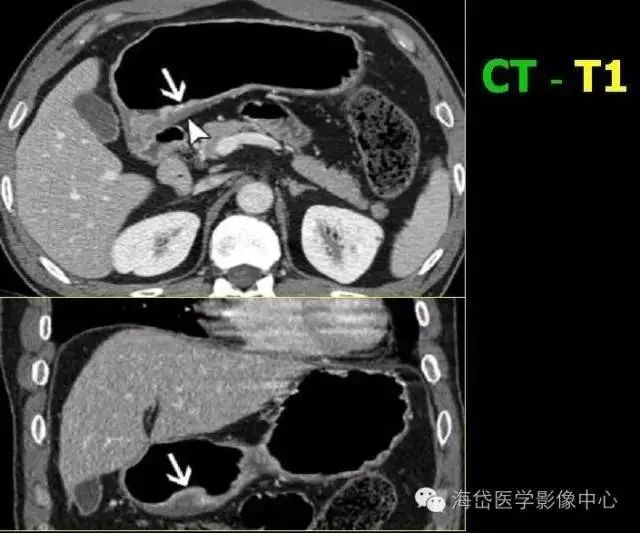

T1:低密度的粘膜層保持完整。

T2:胃壁增厚,低密度帶中斷,外輪廓光滑,周圍脂肪層清晰條索影少于1/3。